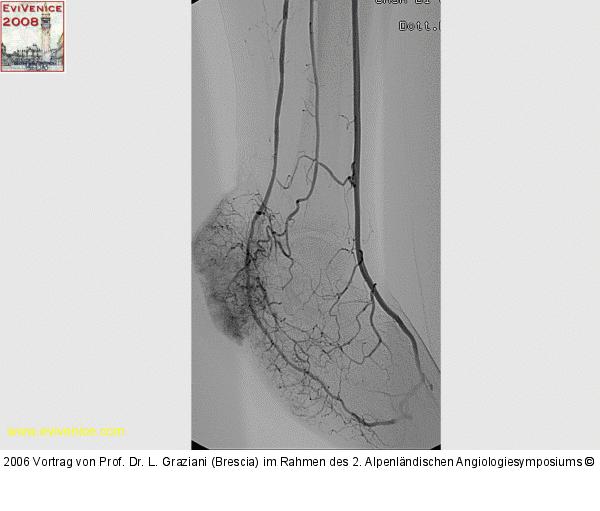

PTA of the foot arteries in diabetics: Extremities Extreme Angioplasty

Abbildung 26: Revaskularisation